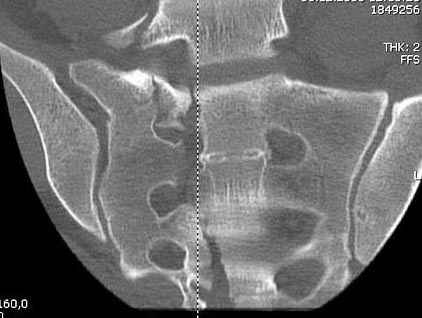

Здесь слайды случая больного с политравмой, включающей сегментарный перелом бедра и повреждение таза с нарушением тазового кольца, разрыв симфиза и перелома крестца зон 2 и 3.

На множественных слайдах важные моменты операции. Хотел бы подчеркнуть, как важно иметь возможности всех необходимых ренгенограмм, включая компютерную томографию и стандартных внутритазовых рентгенограмм (инлет и оутлет).